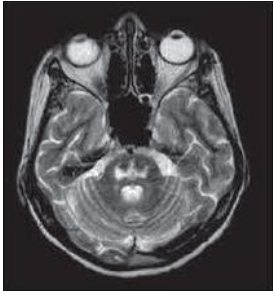

Paciente, 56 anos, internada em leito de UTI devido a complicações da Covid-19, evoluindo com várias intercorrências ao longo dos seus 24 dias de internação hospitalar, como diversos distúrbios hidroeletrolíticos, com necessidade de correção. A paciente evoluiu com tetraparesia espástica e realizou o seguinte exame de imagem:

Enunciado 2606788-1

Assinale o provável diagnóstico da paciente.